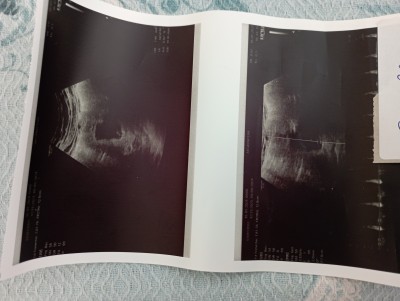

Adet tarihim 16kasım doktor 2aralık olarak değiştirdi geç döllenme olmuş bugün 9 hftalık olmuştu

Arka tarafa yerleşmiş dedi kalp atışı boğuk bi şekilde duydum çok az dinlettiimage

Gebelik haftası 6+5